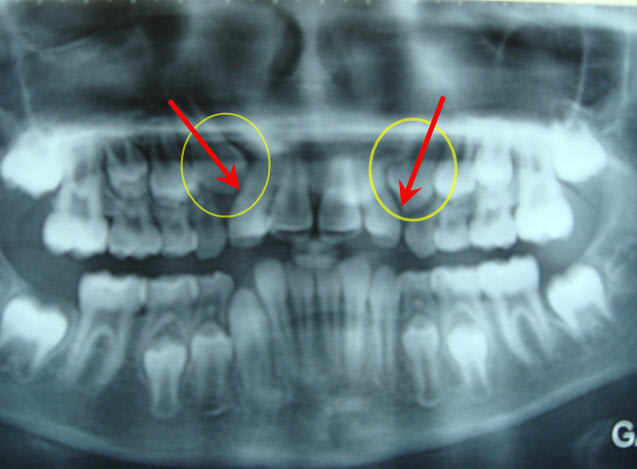

petit fille (10 ans)qui n'a soit disant jamais sucé son pouce (j'en doute) vu la poussée du prémaxillaire) ou magnifique travail de la langue

et maman vient pour que l'on remettre les incisives de la petite à leur place, petite exigeance , elle ne veux rien de fixe, mais je pense pouvoir eventuellement la convaincre.

succion de la lévre inférieure+plan terminal qui nous oriente vers une future classe II+manque de place pour l'éruption des canines supérieures(signe de Quintero),j'aurais proposé un lip bumper fixé sur les molaires supérieures.